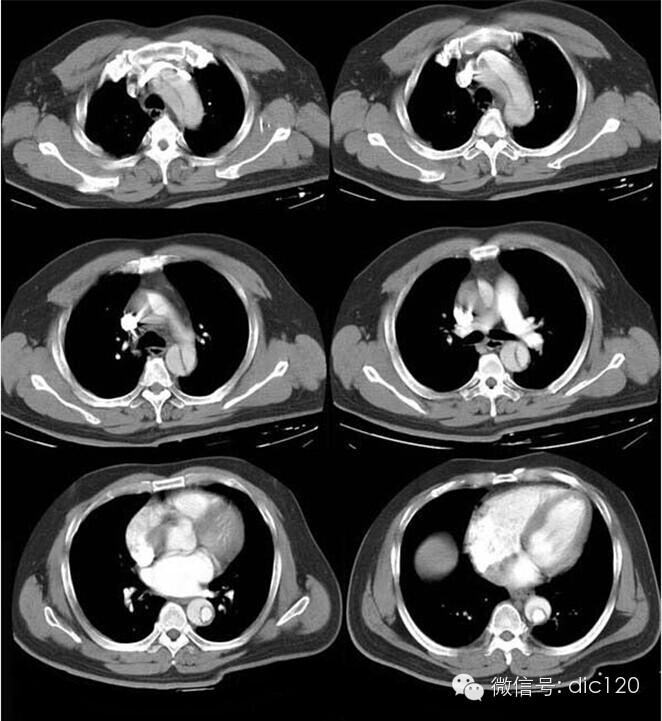

胸主动脉夹层动脉瘤CT病例影像诊断

胸主动脉夹层动脉瘤CT病例影像诊断分析

胸主动脉夹层动脉瘤(DeBakey Ⅰ型)